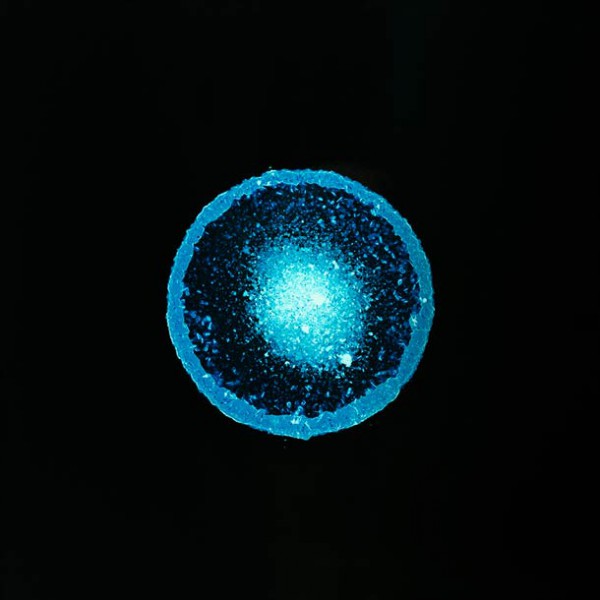

valium